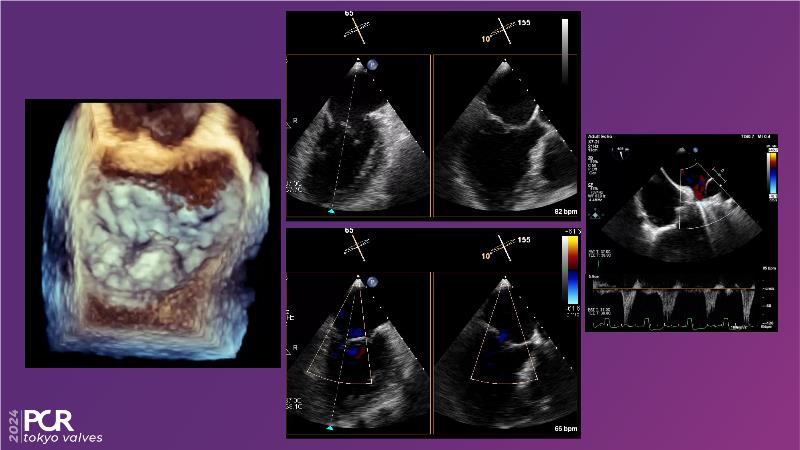

Watch this session to get an overview of a new TEER device, follow the step-by-step procedure related to initial experiences with this device for a Japanese patient with degenerative mitral regurgitation, learn about the latest data from RCT and registries, and follow discussions of challenging TEER cases!

- To understand how novel TEER device provides new possibilities in TEER

- To learn procedural step-by-step of novel device